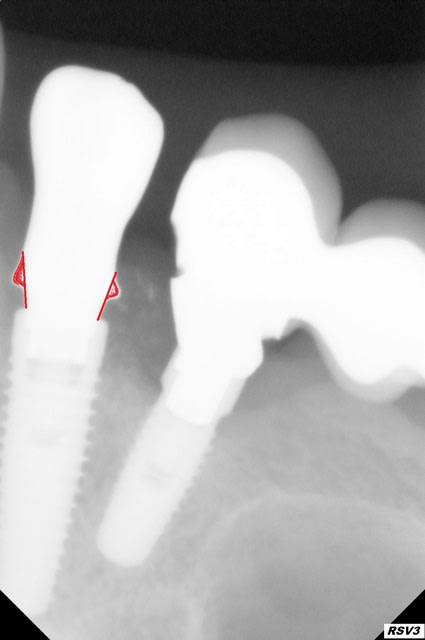

J'ai reçu ce matin une chape d'une 13 trans vissée sur nobelactive et le prothésiste me livre cela ...comment vous trouvez cette chape?

Bon je veux bien que le pied de la 12 soit plus large pour faire une émergence esthétique mais au niveau biologique bof ... vous en pensez quoi alors ?

Je suis seul a trouver cette collerette bizarre ? Ne va t elle pas creer une inflammation ?

et si la collerette était un mm plus bas ce serait sans doute mieux. Es-tu sûr que ton transfert d'empreinte était bien en place?

Pas bon,pourquoi envisager de visser ça? Qui a mis l'analogue dans le pilier empreinte,toi ou lui? ou alors il a fabriqué sur un mauvais diamétre d'analogue? ou sur un analogue d'une autre marque..

analogue de mauvais diamètre comme tu y vas ....le platform switching tu connais où pas :))) Bon effectivement cela repart.

J'avais pas vu que ton os est au niveau du col..ok je sors:)

La collerette ne sert probablement à rien. La chape est en titane ?

La colerette doit servir en fait de support pour la céramique

c'est pas forcément mauvais, la collerette supportera la céramique comme dit plus haut, mais on a quand meme l'impression que ta chape descend pas à fond. c'est pareil sur le modèle? ta chape parrait pas bien polie, peut etre une rugosité l'empeche de descendre à fond.... Mais vu l'inflammation créée par le bridge, il y a fort à parier que tu auras une recession bientot, et la partie transgingivale va apparaitre et ca deviendra inesthétique. Dans une situation comme celle ci, privilègie un pillier zorcone pour pallier au futur problème. Mais je savais meme pas qu'on pouvais faire de la coulée avec des implants au niveau du pilier, je fais (mon prothésiste fait) toujours de l'usinée. ton platform switching c'est bien, mais si tu as un microleakage à cause d'un mauvais effet cone morse dû au fait que ce soit de la coulée et non de l'usinée, le bénéfice du platform switching sera dérisoire. amha .